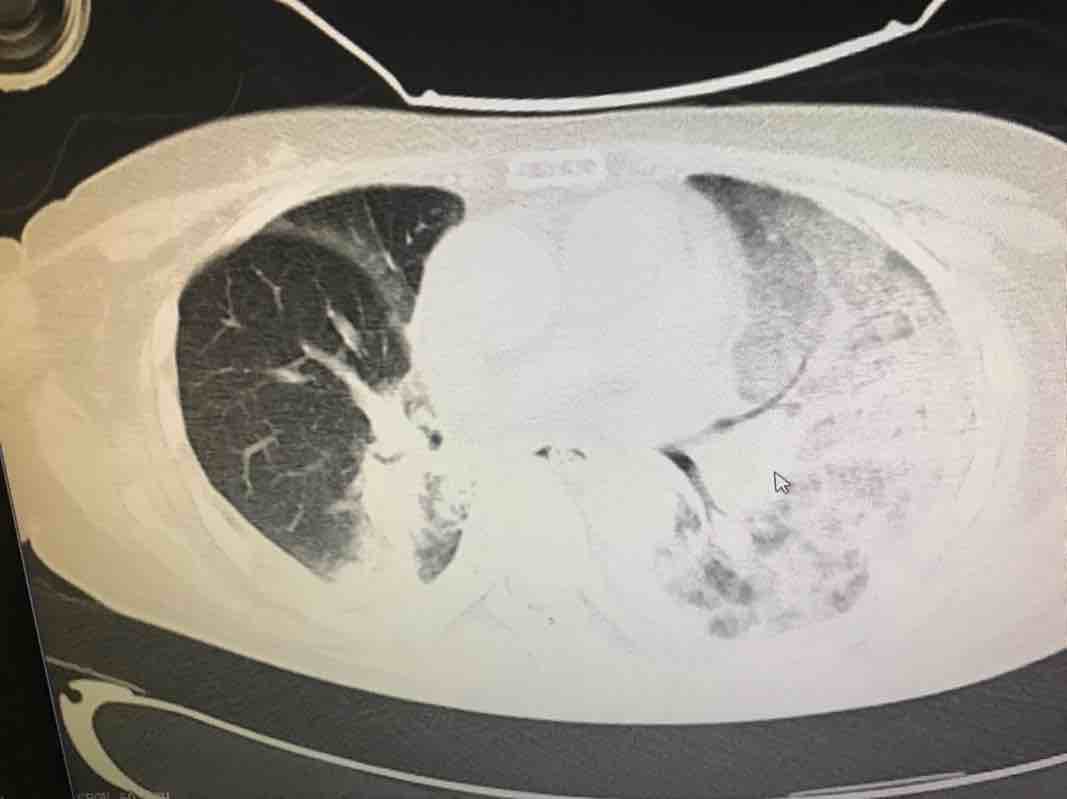

陈波医生看看这个用PD1之后的间质性肺炎的图你就了解了

这是省级医生会诊后说是靶向药引起的间质性肺炎用激素冲后的一个礼拜的结果 陈医生您好 能不能从这些结果看是细菌感染还是靶向药引起的间质性肺炎呢

陈波医生行程中匆匆看了 片子的印象像靶向药引起的间质性肺炎,激素用了几天了